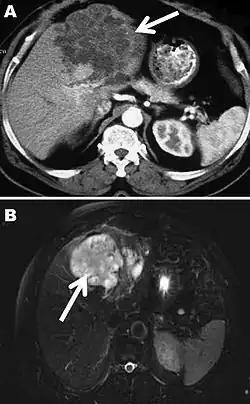

The diagnosis of polycystic echinococcosis involves isolating the protoscoleces during surgery or after the patient's death in order to identify E. vogeli. Imaging, such as ultrasound and CT scans, can also be used to identify polystytic structures, but this method is not preferred as images are similar to other types of echinococcosis and liver cancer. New studies show that PCR may identify E. vogeli in the patient's tissues.[5]

Disease staging